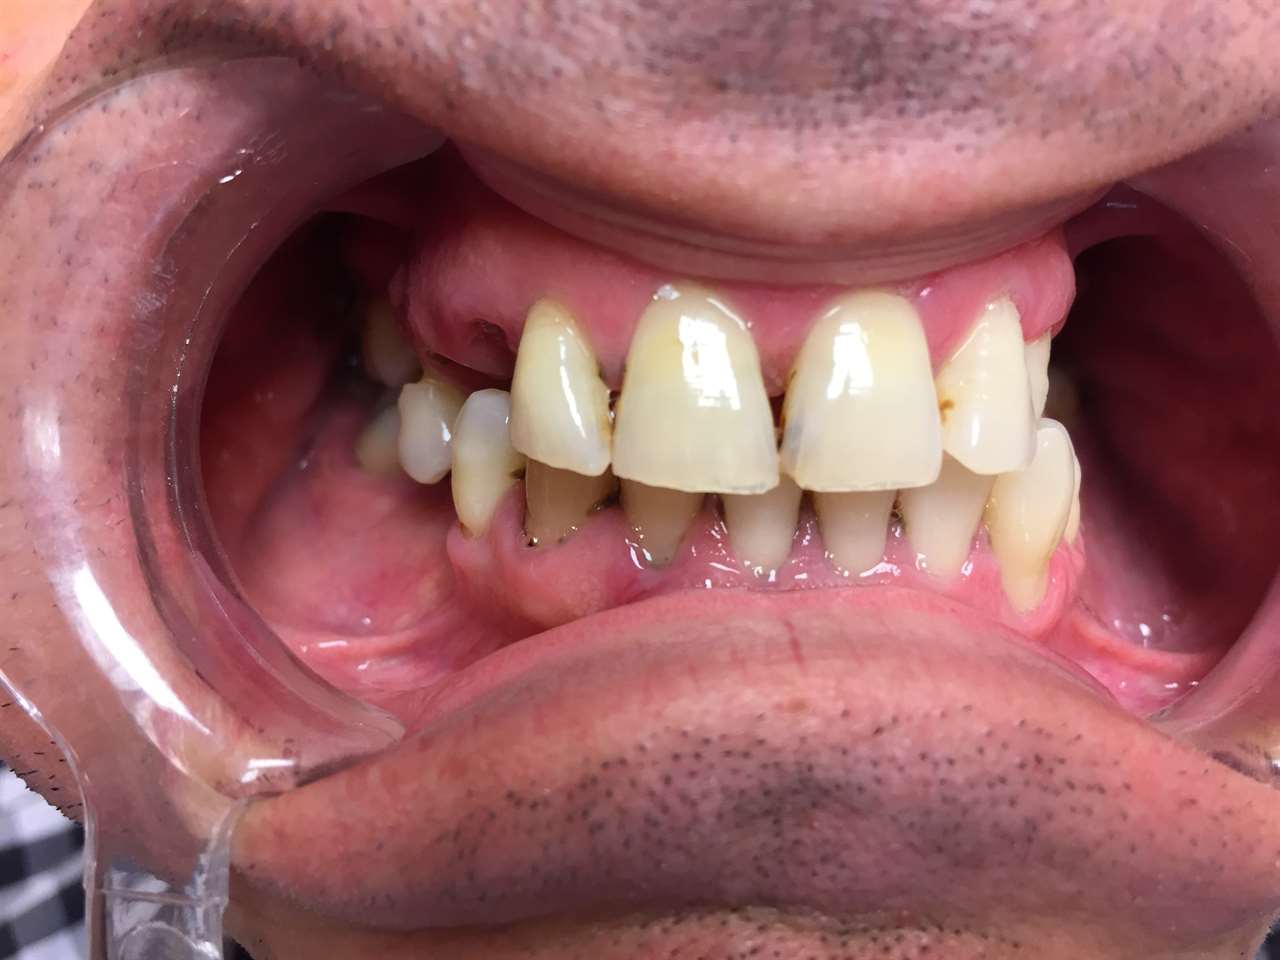

Elhanyagolt fogsor cseréje 2 nap alatt

2 nap alatt varázsoltuk ezt a szép esztétikus alsó, felső körhídat implantátumokkal megtámasztva a korábban elhanyagolt szájba. Az 1. nap 26 fogat távolítottunk el, mert annyira rossz állapotban voltak, és rögtön azonnal terhelhető IHDE svájci implantátumokat raktunk be, fentre 8, lentre 6 darabot. A sebeket összevarrtuk és intraorális szkennerrel digitális lenyomatot vettünk. 2 nap múlva pedig beragasztottuk a kész PMMA műanyag körhidakat. Dr. Kelemen Péter és a Symbion Fogtechnika munkája.